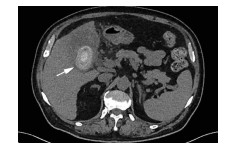

肝病超声诊断指南

中华医学会超声医学分会, 中国研究型医院学会肿瘤介入专业委员会, 国家卫生和健康委员会能力建设和继续教育中心超声医学专家委员会

2021, 37(8): 1770-1785. DOI: 10.3969/j.issn.1001-5256.2021.08.007

超声检查无创、实时、价廉,无辐射、便于反复进行,是最常用的肝脏影像学检查方法。近年来,超声检查新技术如超声造影、弹性成像发展迅速,可有效鉴别肝内占位性病变性质、评估肝纤维化和门静脉高压程度以及监测肝病治疗效果,在临床肝病及其介入治疗中发挥重要诊断价值。本指南规范了肝病多模态超声技术(灰阶超声、彩色多普勒超声、超声造影、弹性超声)检查的仪器调置、患者准备及医生检查方法;对肝脏弥漫性病变(炎性病变、纤维化、硬化)、多种占位性病变及肝病介入操作的多模态超声技术诊断标准进行了定义和规范,同时推荐了超声监测周期及肝脏疾病超声诊断报告书写规范。